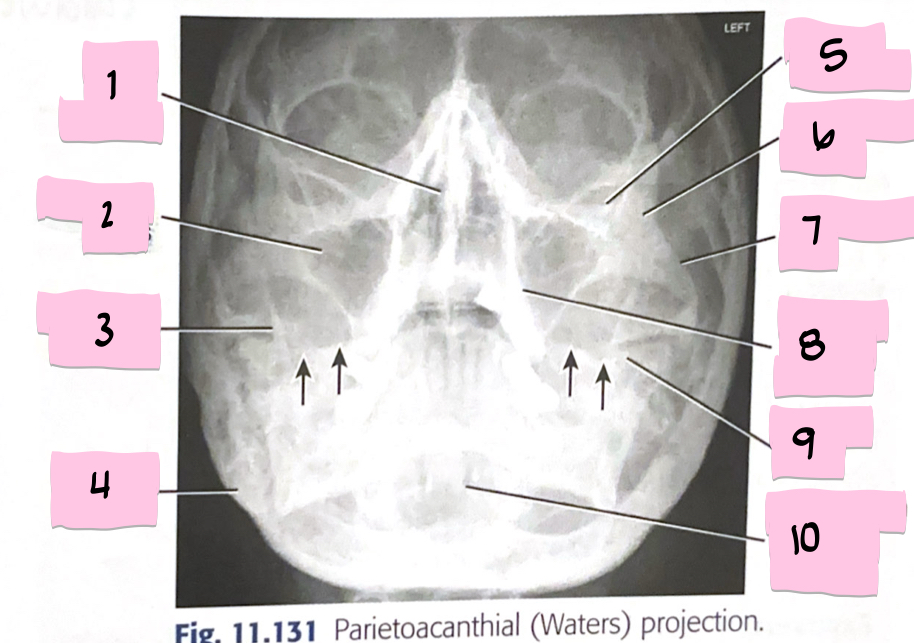

What is 1 pointing to?

Bony nasal septum

What is 2 pointing to?

Maxillary sinus

What is 3 pointing to?

Coronoid process

What is 4 pointing to?

Mastoid process

What is 5 pointing to?

Inferior orbital rim

What is 6 pointing to?

Zygomatic bone

What is 7 pointing to?

Zygomatic arch

What is 8 pointing to?

Maxillary alveolar process

What is 9 pointing to?

Petrous ridge

What is 10 pointing to?

Dens within foramen magnum